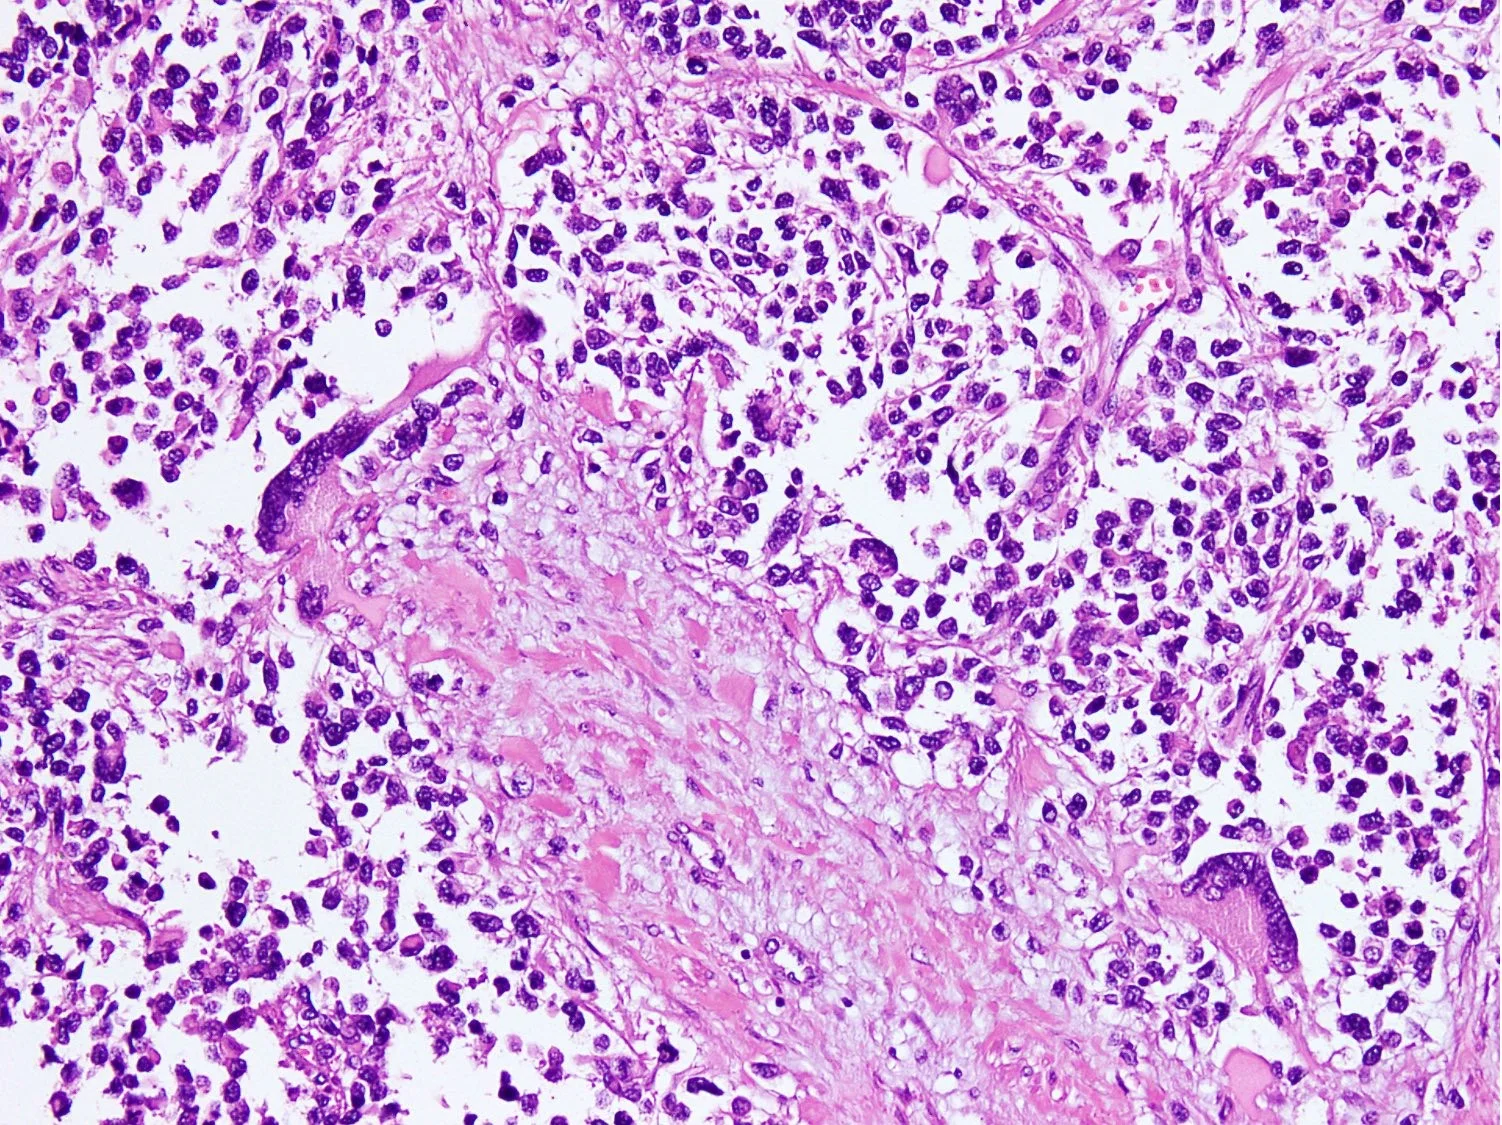

دکتری به نام پاتولوژیست نمونههای بیوپسی را زیر میکروسکوپ بررسی میکند تا ببیند آیا سلولهای سرطانی در آنها وجود دارد یا خیر. اگر سرطان پیدا شد، قدم بعدی این است که بفهمید آیا سرطان RMS است یا خیر. در موارد نادر، پاتولوژیست میتواند ببیند که سلولهای سرطانی دارای خطوط عضلانی کوچکی هستند که به تایید RMS بودن سرطان کمک میکند اما اغلب برای اطمینان از تستهای آزمایشگاهی دیگری نیاز است.

آسیب شناس ممکن است از رنگهای خاصی روی نمونهها برای شناسایی نوع تومور استفاده کند. این رنگها حاوی پروتئینهای خاصی (آنتی بادی) هستند که به مواد موجود در سلولهای RMS متصل میشوند اما به سایر سرطانها نمیچسبند. رنگها ماده مشخصی را تولید میکنند که زیر میکروسکوپ قابل مشاهده است. این به پاتولوژیست اجازه میدهد تا بداند که تومور یک رابدومیوسارکوم است.

اگر تشخیص RMS داده شود، پاتولوژیست همچنین از تستهای آزمایشگاهی ویژه برای کمک به تعیین نوع RMS استفاده میکند. این امر مهم است زیرا بر نحوه درمان سرطان تأثیر میگذارد. برای مثال، رابدومیوسارکوم آلوئولار (ARMS) که تمایل به تهاجمیتر بودن دارد، معمولاً به درمان شدیدتری نسبت به رابدومیوسارکوم جنینی (ERMS) نیاز دارد. بخش مهمی از این آزمایش، جستجوی تغییرات ژنی یا کروموزومی در سلولهای سرطانی است، مانند مواردی که در مبحث چه عواملی باعث رابدومیوسارکوم میشود؟ گفته شد.